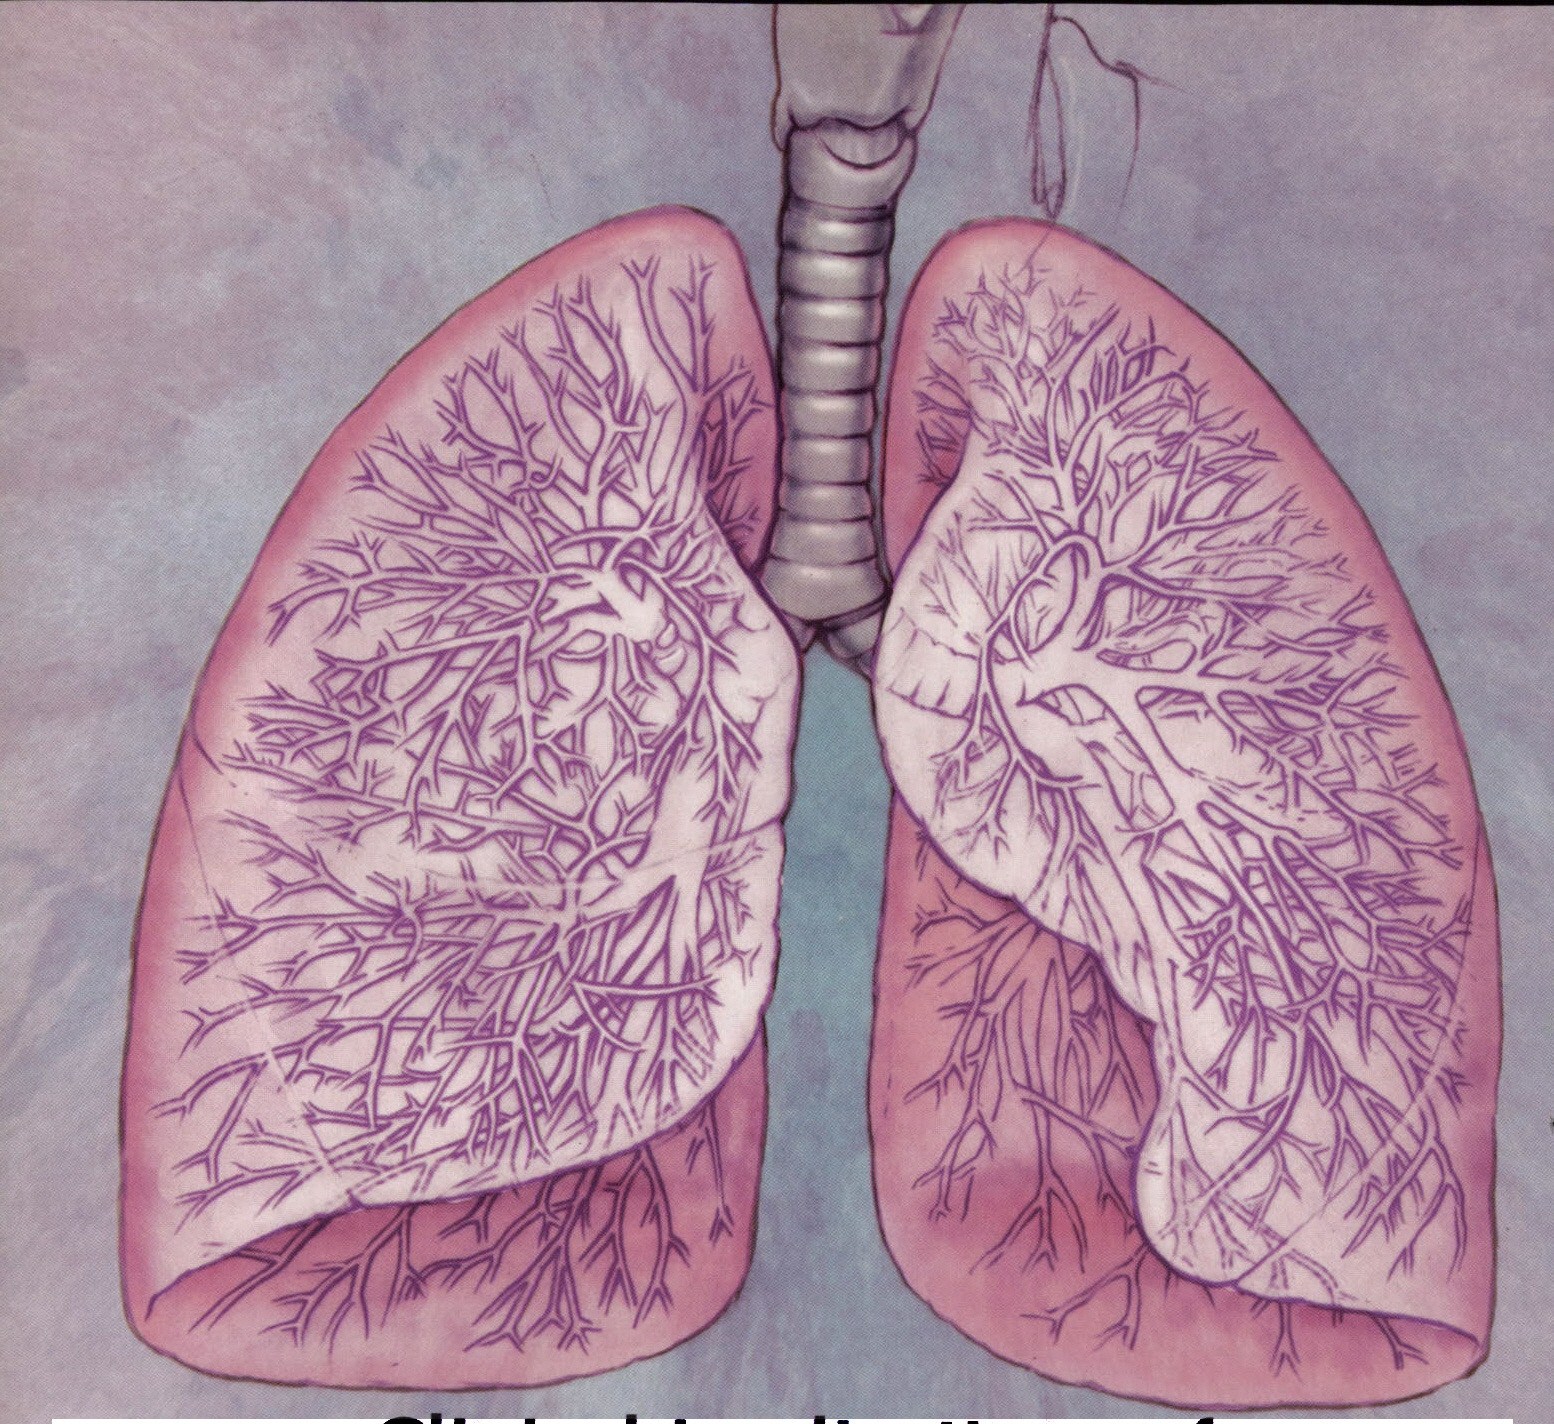

Лёгкие человека: Учебные картинки для детей